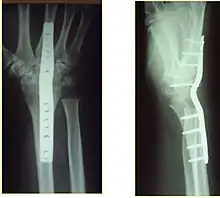

X-rays of pins across a distal radius fracture: Notice the ulnar styloid base fracture, which has not been fixed. This patient has instability of the DRUJ because the TFCC is not in continuity with the ulna.